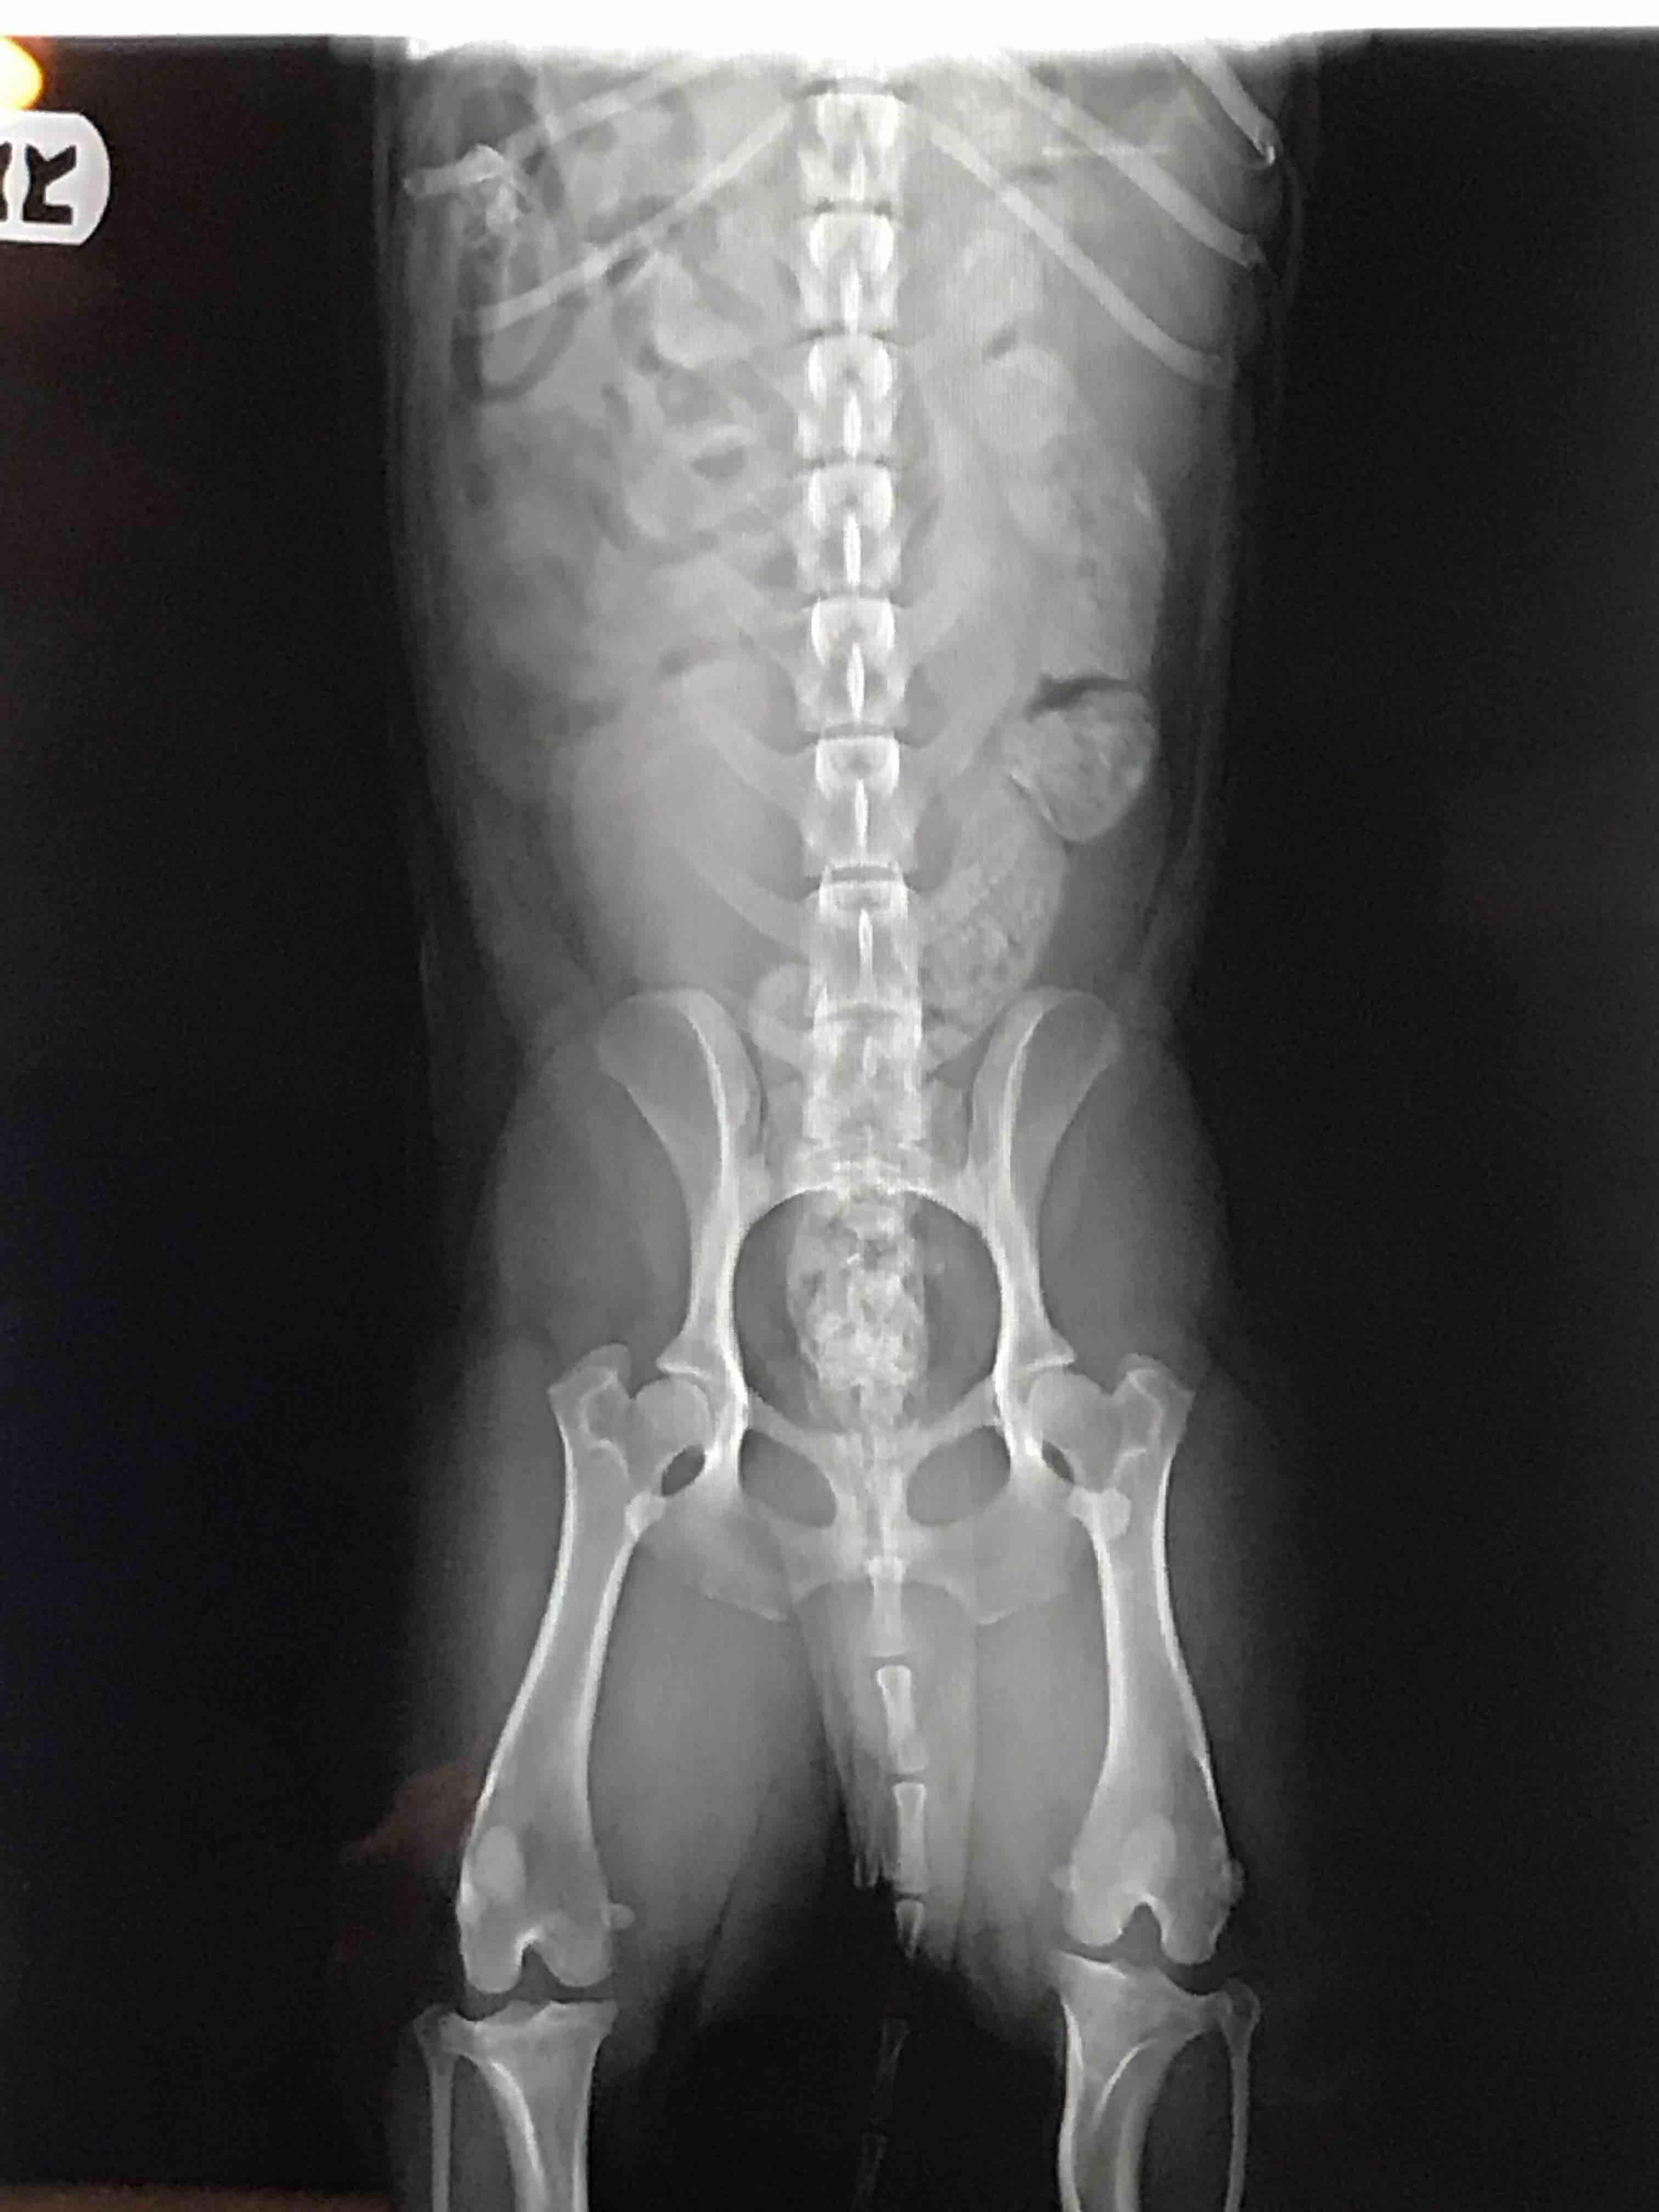

Do my dog's hip x-rays look bad? Should I get a second opinion?

Pet's info: Dog | Mixed Breed | Male | neutered | 3 years and 2 months old | 20.08 lbs

I wanted to know if his hips look bad? I was told not to worry about them but i have a gut feeling his hips don’t look good. Should i have them redone and get a second opinion? Or can you tell from these rads that the hips aren’t to great?

From what I can see his hips look pretty good, there is good coverage of the femoral head by the hip socket, the femoral heads seem to be pretty smooth and rounded, but if you want a second opinion, you can ask your vet for copies of the x-rays or ask them to send them to a veterinary radiologist for an expert eye.